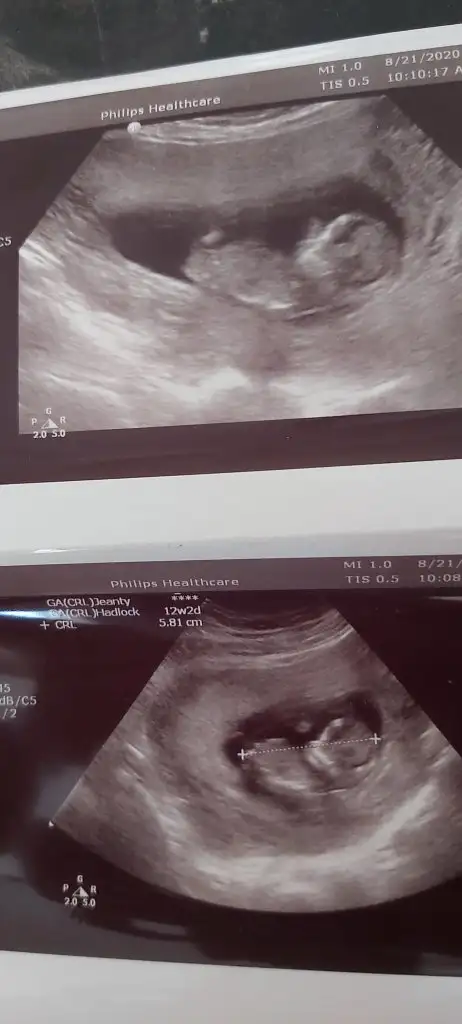

Google den girdim oldu harbiden teşekkürler : ) bakın bakalım benim bebeğimin cinsiyetine bir de bütün fotoğraflarda aynı mı yani kızsa hepsinde kız mı görünüyor erkekse hepsinde erkek mi görünüyor onu söyleyin ben neden hepsinde farklı gördüm acaba.. Ayrıca USG görüntüleri 11 ve 12. Haftalar arasına ait..Yeni üyeyim fotoğraf nasıl yükleniyor acaba yaa bulup da gönderemiyorum yardımcı olur musunuz?? Dosya ekle seçeneğini seçiyorum hiçbir ekran gelmiyor..

Hepsi kız görünüyorGoogle den girdim oldu harbiden teşekkürler : ) bakın bakalım benim bebeğimin cinsiyetine bir de bütün fotoğraflarda aynı mı yani kızsa hepsinde kız mı görünüyor erkekse hepsinde erkek mi görünüyor onu söyleyin ben neden hepsinde farklı gördüm acaba.. Ayrıca USG görüntüleri 11 ve 12. Haftalar arasına ait..

Yaaa gerçekten miiiiii... Ama doktor bana erkek dedi hatta pipisini bile gösterdi.. Bende hep kızım olsun istiyorum acaba kız mı ki yaaa... Şuan 14 haftalığım doktor tam 12 haftalıkken dedi erkek diye...Hepsi kız görünüyor

Ben kız istediğim için doktora emin misiniz belki değişecek ne belli dedim doktor bana güldü evet yanılma payı olabilir 15 16. Haftalar arası en net denilir ama ben sana yine erkek diyeceğim dedi yaaa.. Ama çok acayip istedim ki kızım olsun.. O yüzden belki sizden kız çıkar diye sormak istedim. Teşekkür ederim bakalım ne çıkacakKıza gibi nubu12 hafta cok erken 15-16 olsa doğrudur diyecemde tabi Dr daha detaylı bakar birdaki randevuda netleşir